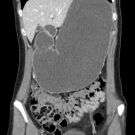

A 49-year-old man presented to the emergency department with a 1-day history of progressive bilateral lower-extremity weakness and an inability to bear weight.